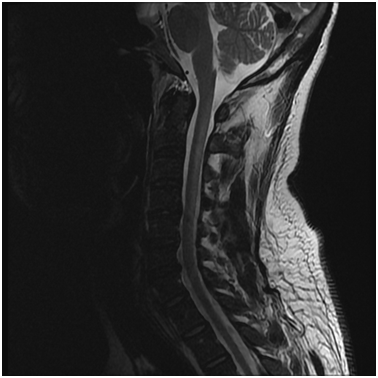

MRI of the cervical spine showed long hyperintense cervical lesion extending from the Cervicomedullary junction to C7, mainly in the dorsal column (Figure 3,4). MRI Dorsal, Lumbosacrsal spine and Brain were normal.

Figure 3 MRI Cervical spine, T2-weighted image (sagittal view) showing a long hyperintense lesion extending from cervicomedullary junction till C7 affecting the dorsal aspect (white arrows).

His blood cell count and blood film returned back to normal within 2 weeks of treatment initiation. Serum B12, homocysteine and MMA returned back to normal within 3 months. His motor strength, gait and balance showed subsequent marked steady improvement at 1-month, 3-months and 6-months follow- up visits. MRI of the cervical spine with contrast was repeated after 3 months of treatment and showed complete resolution of the cervical lesion (Figure 5).

Figure 5 Follow up MRI Cervical spine (sagittal view) with and without contrast showing complete resolution of the cervical myelopathy.

MRI is an important and sensitive tool in diagnosis of SCD; on sagittal images, a vertical segment can be seen at the posterior aspect of the spinal cord and B12 deficiency should be suspected in cases with longitudinally extensive transverse myelitis (LETM). On axial images, bilateral paired areas of T2 hyperintensity are seen as an “inverted V” or “inverted rabbit ears” (Figure 4) in the dorsal columns. Lateral column involvement is seen in severe cases. Contrast enhancement is uncommon. Signal abnormalities are usually reversed after treatment within a few months. MRI of the brain may show abnormal signal intensity on T2-weighted images in the cerebral white matter.8